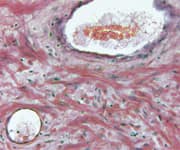

The most common approach is called transrectal ultrasound biopsy. The main problem with this technique is that it’s inadequate for assuring that all of the tumor will be detected, and misses up to 46% of significant (high-grade) cancers.7,12 Studies have shown that transrectal ultrasound biopsies bear little resemblance to the actual pathological findings when the entire gland is removed, which clearly indicates room for improvement.12,13

First, they began using a highly accurate means of examining the prostate gland in three dimensions and obtaining biopsy specimens from the entire bulk of the gland. A technique called three-dimensional prostate mapping biopsy, 3D-PMB, provides more accurate information about a tumor’s extent and location compared with a standard transrectal ultrasound biopsy.12,15

This three-dimensional prostate mapping biopsy is extraordinarily accurate and painless, and it does not involve puncturing the rectal wall. This sterile procedure greatly lowers the chance for life-threatening sepsis and debilitating prostatitis, which are sometimes the result of standard transrectal ultrasound biopsies.